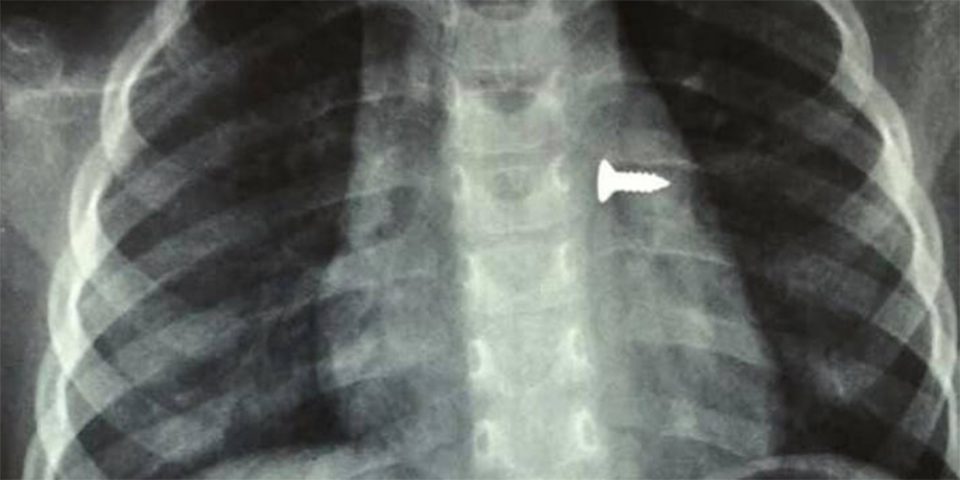

Κοριτσάκι μόλις 3 ετών στο Ηράκλειο της Κρήτης κατάπιε βίδα η οποία κατέληξε στον αριστερό της πνεύμονα.

Σύμφωνα με τα όσα έκανε γνωστά ο αναπληρωτής καθηγητής ΩΡΛ της Ιατρικής Σχολής Κρήτης, Μανώλης Προκοπάκης, το παιδί μεταφέρθηκε στο νοσοκομείο και αμέσως του έγιναν ακτινογραφίες που έδειξαν πού βρισκόταν η βίδα σύμφωνα με το cretapost.gr.

Οι γιατροί άμεσα οδήγησαν το κορίτσι στο χειρουργείο και μετά από αρκετή ώρα κατάφεραν να αφαιρέσουν την βίδα. Ο κ. Προκοπάκης σε ανάρτησή του στα social media ανέφερε: «Πολύ επείγον χειρουργείο! Πριν από λίγο. Αφαίρεση βίδας από αριστερό βρογχικό δέντρο τρίχρονου κοριτσιού. Πολύ επικίνδυνο…».